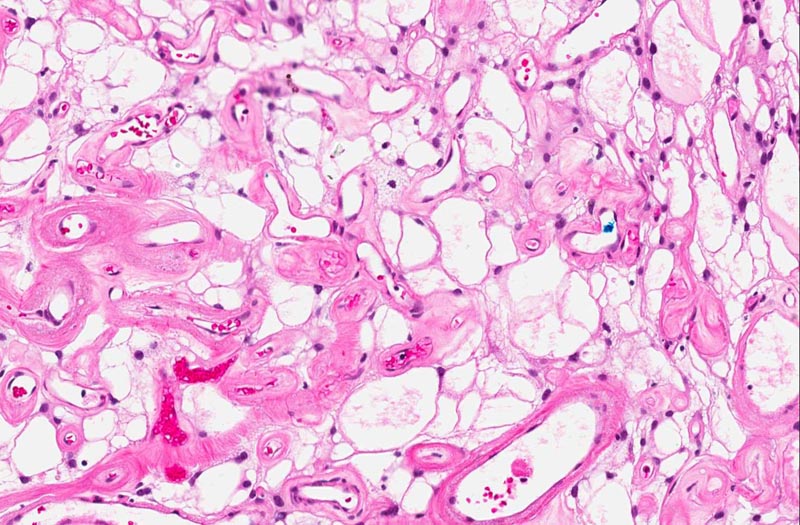

Slide #2 represent the tissue that are

submitted subsequently. The histopathology between this sample and

slide #1 is essentially similar but the there are a lot more highly

sclerotic blood vessels. Some calcifications consistent with

psammoma bodies are present (area 3). The sclerotic blood vessels

dominated the picture. In between the sclerotic vessels are

triangular to irregular nest of stromal cells (area 3). Microcyst

formation is rather common (area 4 and 5).

The overall histopathologic picture is

that of an angiomatous meningioma. These tumor are featured by

hypervascularity and often with degenerative changes of the vessels

including vascular hyalinization as illustrated in this case. The

nuclei tends to undergo degenerative atypia (ancient changes)

featured by slightly enlarged, homogeneously hyperchormatic nuclei

without prominent nucleoli and not associated with increased

mitosis. The neoplastic meningothelial proliferation often has microcystic

pattern as illustrated here.